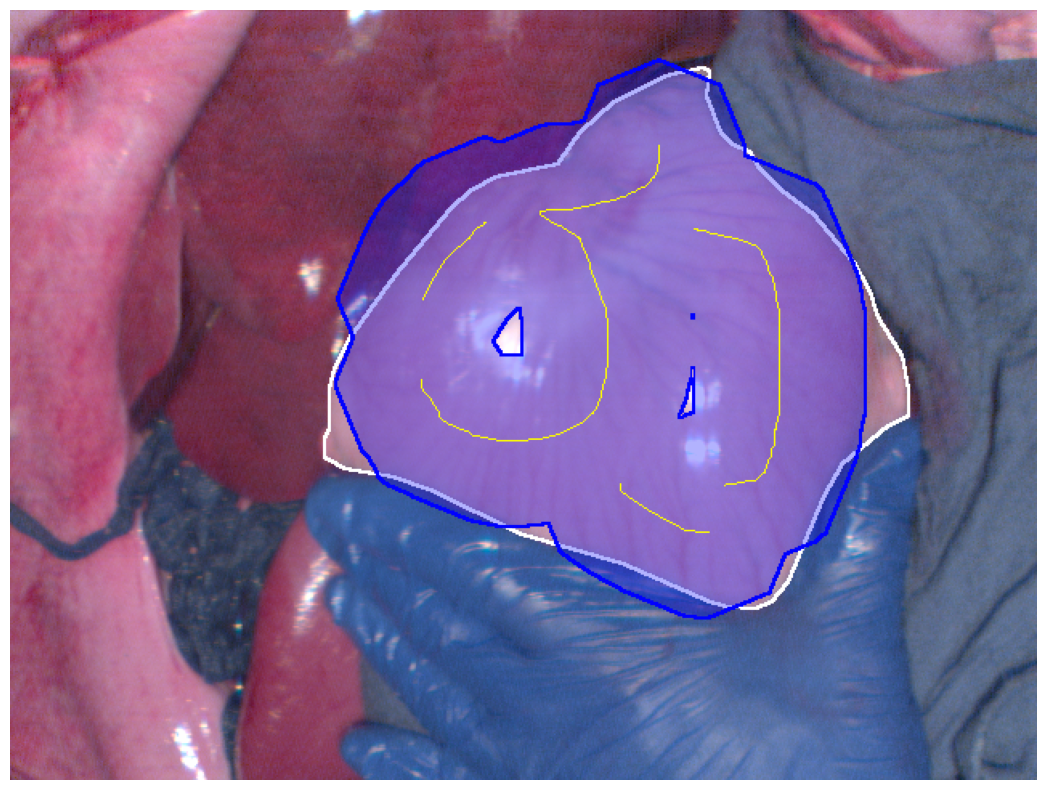

Refer to caption

(a) Deep learning-based feature best Dice segmentation result

Figure 2: Segmentation results (blue regions) at the best Dice coefficient for different methods and ground truth (white regions), along with the curves of Dice coefficient variation with threshold adjustments.

In Fig. 2, the segmentation results at the best Dice for the four different methods are displayed, along with the variation in Dice coefficients with threshold adjustments. From Fig. 2e, it can be seen that the Euclidean distance method has the lowest maximum Dice score of 0.914. The methods using geodesic distance maps generated from hyperspectral images and reconstructed RGB images achieve similar maximum Dice values, both higher than the Euclidean method. The deep learning-based feature geodesic distance map method achieves the highest maximum dice coefficient.

For the 575 images in P086, automated scribbles were generated by skeletonizing the annotation results, and segmentation results were produced using pre-mentioned four different methods. Among these, the deep learning-based feature geodesic distance map method achieved the highest average max Dice score of 0.842, demonstrating its superior performance.